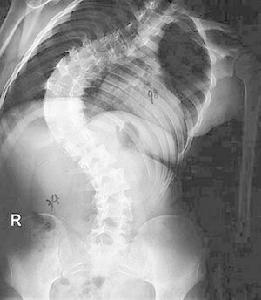

3.X線檢查以確定有無半椎體畸形,除外後天性病變,並按Cobb法測量側凸畸形角度。同時還應對脊柱發育程度進行估計。必要時應行去鏇轉位攝片。

1.脊柱側凸:刀背樣畸形、半椎體畸形。

初診的脊柱畸形一般以背部畸形為主要症狀,表現為駝背、姿態不對稱,雙肩不等高、身材矮小等,嚴重的脊柱畸形由於胸腔容積下降導致活動耐力下降、氣促、心悸等,部分病人可出現腰痛。